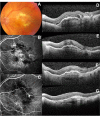

Purpose: To report the effect of intravitreal ranibizumab therapy for serous and vascular pigment epithelial detachments (PED) associated with choroidal neovascularisation (CNV) secondary to age-related macular degeneration (AMD).

Methods: In a prospective study, best-corrected visual acuity (BCVA) and optical coherence tomography (OCT) data were collected for 62 eyes of 62 patients, with serous or vascular PED associated with CNV secondary to AMD. Intravitreal ranibizumab 0.5 mg was administered with a loading phase of three consecutive monthly injections, followed by monthly review with further treatment, as indicated according to the retreatment criteria of the PrONTO study. The change in visual acuity and PED height from baseline to month 12 after the first injection was determined.

Results: Sixty-one eyes of 61 patients (one of the patients developed retinal pigment epithelial tear and was excluded from the study) were assessed at the 12-month follow-up examination. There were two types of PED, including vascular PED in 32 patients (Group A) and serous PED (Group B) in 29 patients. The mean improvement of mean BCVA from baseline to 12 months was 0.09 logMAR (Logarithm of the Minimum Angle of Resolution) in Group A and 0.13 logMAR in Group B. Both groups showed significant improvement of the mean BCVA 12 months after the first injection compared with the baseline value (P < 0.05). In relation to the PED height, the mean decrease of mean PED height from baseline to 12 months was 135 μm in Group A and 180 μm in Group B. Both groups showed significant reduction of the PED height during the follow-up period (P < 0.01). The PED anatomical response to ranibizumab was not correlated with the BCVA improvement in any of the groups. Apart from one patient who developed pigment epithelial tear no other complications were documented.

Conclusion: Ranibizumab is an effective and safe treatment for improving vision in patients with serous and vascular PED, although the anatomical response of the PED to ranibizumab may not correlate directly with the visual outcome.